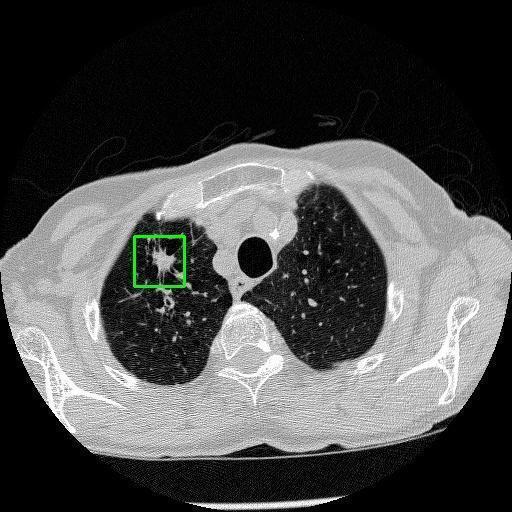

We developed an AI-based system using deep learning models for analyzing lung CT scans to detect and classify pulmonary nodules. We chose the YOLOv11 architecture for its enhanced object detection capability and adapted it specifically for medical imaging, incorporating pixel-level precision and severity classification.

Classification into three severity levels with colored bounding boxes.

Maintaining performance on small, complex features like micro-nodules tested the limits of traditional object detectors.

Designed a severity classification system that categorizes nodules into null, moderate, and severe using colored bounding boxes, assisting in rapid clinical decision-making.